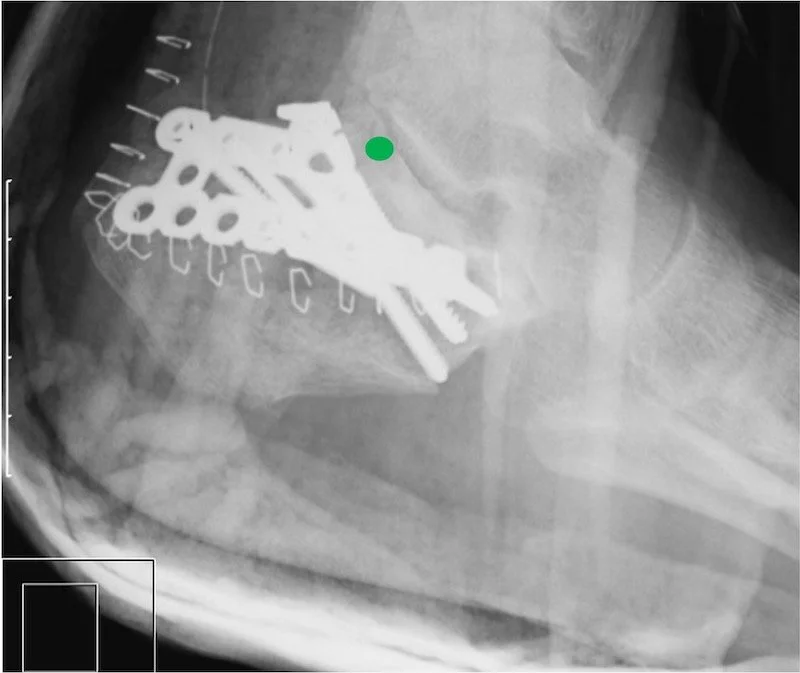

You can see in this picture during surgery that the bone has a black dark area through it , thats how the fracture line looks. When these bones break the bone is crushed into itself and we essentially lose bone shape. During surgery we put it all together as much as possible. Then we apply a large plate that you can see in the next photo tp hold all of the fragments together. As you can see this is a large incision, we prefer not to do it this way so 90 percent of the time we are able to use or minimal incision technique for these bone repairs.

Here is an xray of the same foot with a plate attached after surgery to realign the joint and bones. You can see the curved green line- we were able to put the subtalar joint back into alignment to hopefully prevent progression of arthritis and pain.